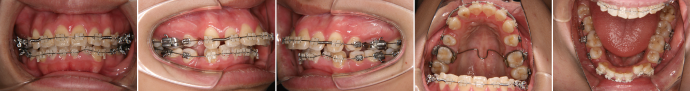

| 主訴 | 前歯の突出が気になる |

| 年齢・性別 | 28歳 / 男性 |

| 治療方針 | 上顎前突及び過蓋咬合。下顎の後退感が顕著なため、口元の突出感が目立つ。下顎前歯の1歯欠損と左側大臼歯に鋏状咬合がある。完全に突出感を改善するのは困難と思われるが、できる限り上顎前歯を後退させる。 ※治療後オトガイ部の緊張がとれて、プロファイルはある程度改善できた。 |

| 抜歯部位 | 上顎左右第1小臼歯、下顎前歯、左右第3大臼歯(親知らず) |

| 使用装置 | 歯科矯正用アンカースクリュー、マルチブラケット装置 |

| 治療期間 | 38か月 |

| リテーナー | 上顎インビジブル、下顎インビジブル |

| 費用 | 840,000円(税別) |